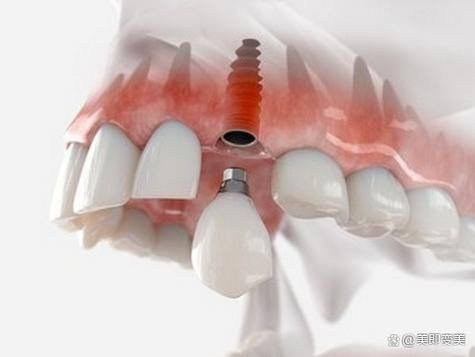

3. 杆卡式种植覆盖义齿:欧忠辉医生擅长杆卡式种植覆盖义齿技术。这种技术适用于牙齿缺失较多的患者,通过种植体与义齿的连接,提高义齿的稳定性和咀嚼功能。欧医生在手术过程中,能够精细地植入种植体,确保义齿的贴合度和舒适度。同时,他还会根据患者的口腔情况和生活习惯,为患者提供个性化的义齿设计,让患者能够更好地适应义齿。

3. 患者王先生,牙齿缺失多年,一直佩戴活动假牙,但佩戴成效不佳,咀嚼功能也受到了较大影响。他找到欧忠辉医生,希望通过种植牙来修复牙齿功能。欧医生为王先生进行了详细的口腔检查和评估,制定了杆卡式种植覆盖义齿的治疗方案。手术过程非常顺利,欧医生精细地植入了种植体,并为王先生安装了合适的义齿。术后,王先生的咀嚼功能得到了明显改善,义齿的稳定性也良好。王先生评价说:“欧医生的种植牙技术非常厉害,让我重新拥有了健康的牙齿。手术过程中我没有感觉到太多的疼痛,术后修复也特别快。现在我可以像正常人一样吃东西了,真的太感谢欧医生了。”